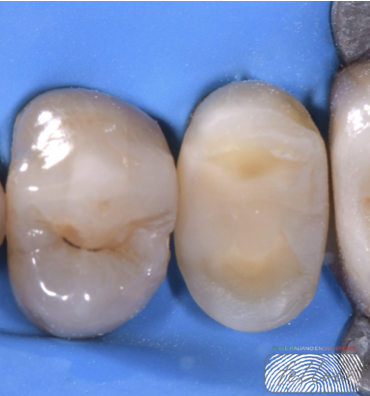

The tooth was prepared for an indirect overlay restoration, preserving healthy tooth structure through a minimally invasive approach.

Fig. 7

Final cementation of the indirect overlay restoration was carried out.Indirect overlays generally show better fracture resistance and higher survival rates compared to large direct fillings on endodontically treated teeth.